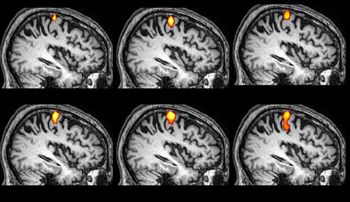

Results from the CRYSTAL-AF study find that nearly one-third of patients who experience cryptogenic stroke may have undetected atrial fibrillation.